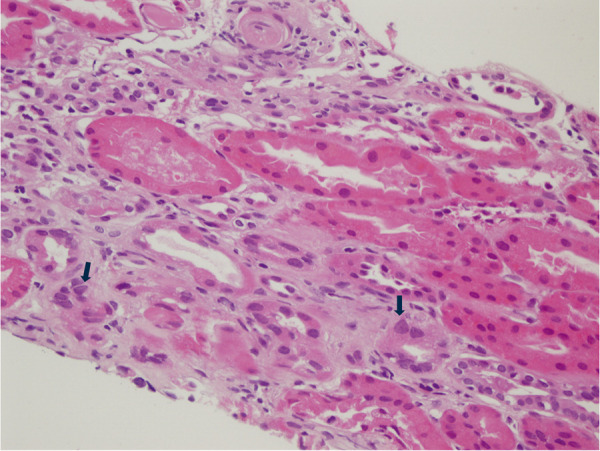

Karyomegalic interstitial nephritis (KIN) is a rare hereditary form of chronic interstitial nephritis that was first described over 50 years ago. It is characterized by karyomegalic tubular epithelial cells and progressive chronic kidney disease, often leading to end-stage renal disease by the fifth decade of life. Recent studies have identified FAN1 mutations as a key genetic contributor, with additional associations to environmental factors and toxic exposures, such as ochratoxin A, alkylating agents, and heavy metals, which may act as potential triggers of the disease. We present a detailed analysis of KIN cases, highlighting genetic diversity, clinical manifestations, and management challenges, complemented by a comprehensive review of the literature.

Abstract Image